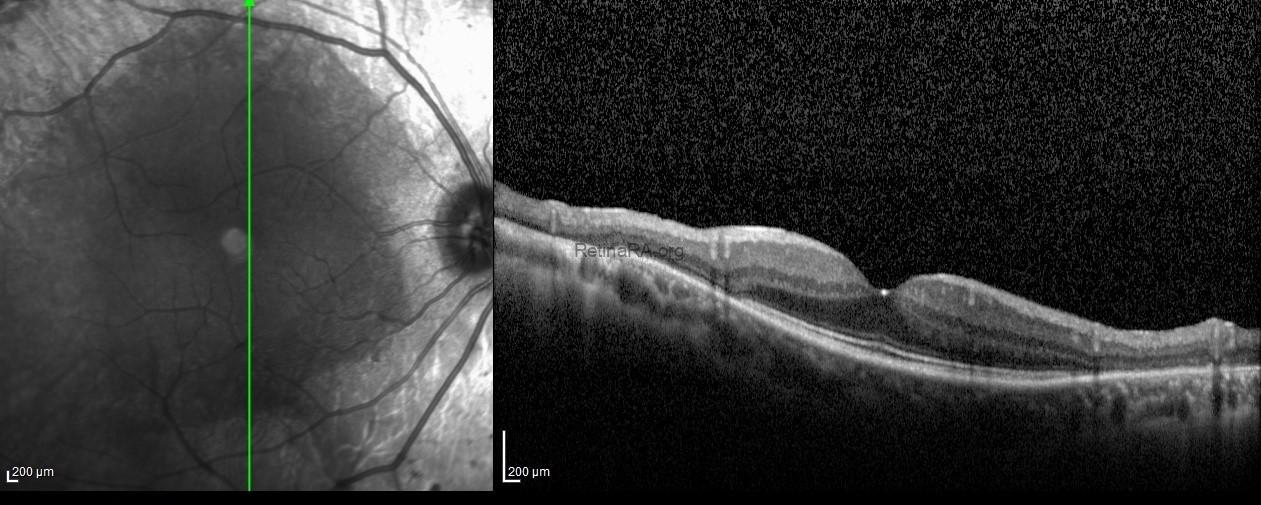

Vertical scans spectral-domain optical coherence tomography exhibited the atrophy of outer retinal layers and retina pigment epithelium at the paravenous areas with the normal retinal microstructure at macular areas in both eyes.